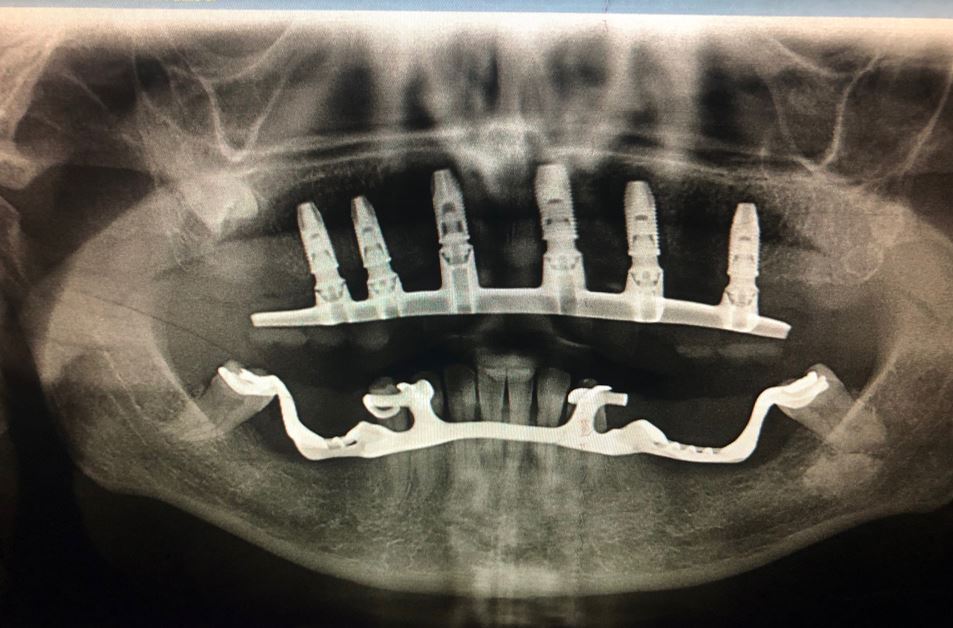

IMPLANTOLOGIA

Nesta área da cirurgia, procedemos à substituição dos dentes perdidos através de implantes dentários certificados. Realizamos cirurgias guiadas, minimamente invasivas, para garantir um maior conforto do paciente.